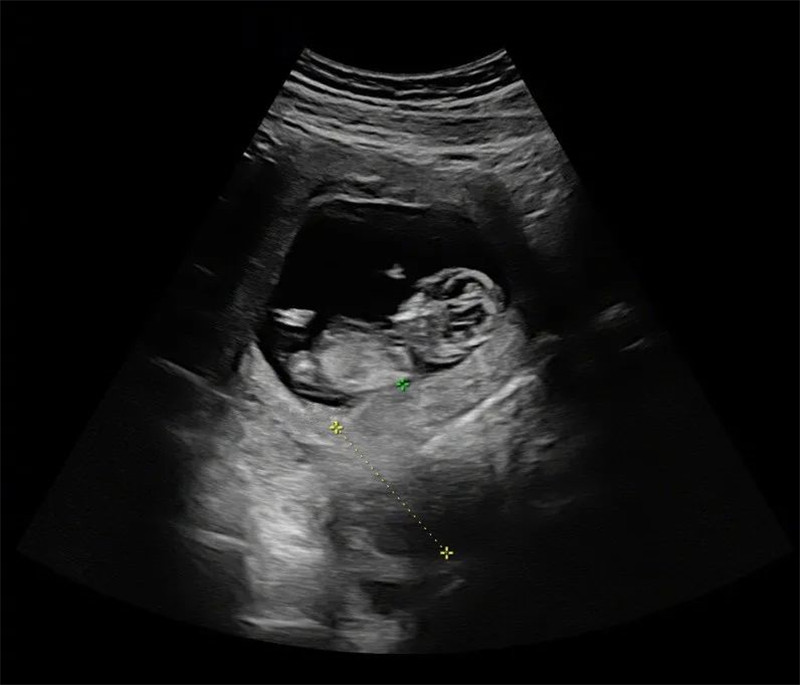

楊佑寧分享喜訊,寫道:“我同我嘅未婚妻Malinda,準備進入人生嘅下一個階段。”然后曬咗兩人親密合照同寶寶嘅B超相。

楊佑寧一直都夢想結婚生子,愿望就系呢個事要喺40歲之前完成。現在突然就實現咗,所以兩個人都開心嘅接受。寶寶預年尾出世。據楊佑寧嘅朋友透露,寶寶啱滿三個月,而楊佑寧好開心向朋友宣布自己要做老豆。